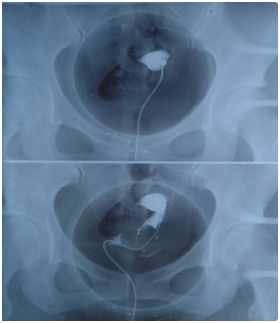

[Photo provided to chinadaily.com.cn] |

Therefore, to avoid the occurrence of an unwanted pregnancy, efficient, long-lasting and reversible contraception is the best choice. If you had a child before and you don’t want to have another baby yet, you can choose the LNG-IUD (levonorgestrel-releasing intrauterine device), CU-IUD (copper intrauterine device) or subcutaneous preparations for contraception. If you don’t have a child, you can choose COC (compound oral contraceptives) for contraception.